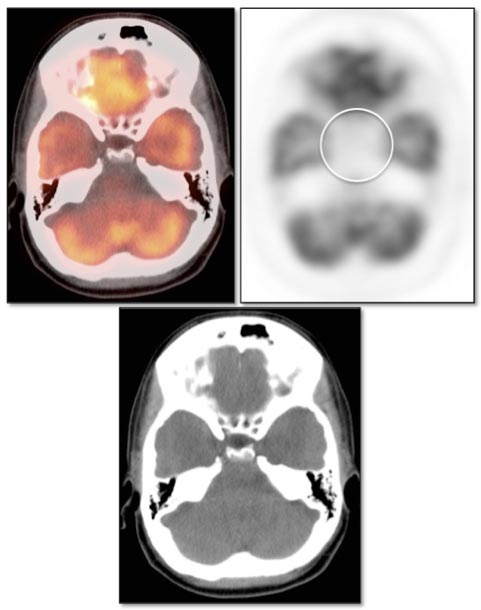

Sella

Due to the extremely intense metabolic activity of the brain, most PET reading software programs will require the reader to manually decrease image intensity to permit adequate evaluation of the brain for potential lesions.

Sella pathology is also best visualized on these “turned down” black and white axial images.

The normal sella typically demonstrates little or no FDG uptake.

- Very mild metabolic activity, without an obvious corresponding CT abnormality, is frequently seen as a normal variant.

- Intense sella uptake, without a corresponding soft tissue density on the co-registered CT images, often represents a pituitary microadenoma.

- Intense sella uptake, with a corresponding soft tissue density on the co-registered CT images, usually represents a pituitary macroadenoma.

Even though most cases of moderate to intense sella uptake do not represent malignancy, MRI correlation is still recommended. In such cases, we generally report:

“Although this uptake can be physiologic or may represent a benign pituitary lesion, MRI correlation is recommended in this case.”